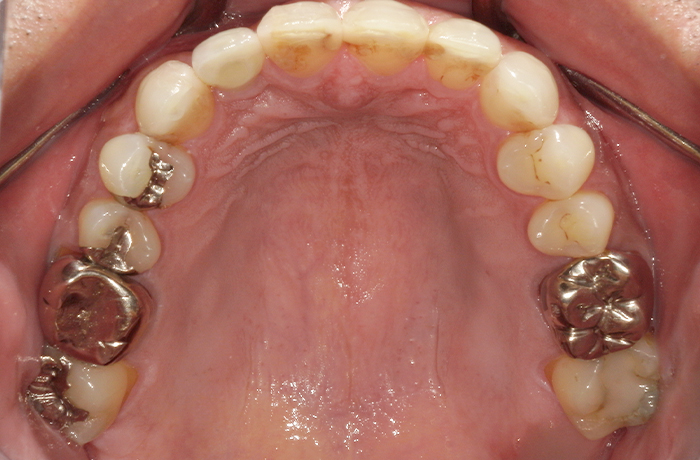

治療前

口腔内写真とレントゲン写真

右上2番は骨吸収が進み、動揺と咬合痛を伴っていました。

保存困難な状態であり、審美的にも歯頚ライン(歯の見えている部分と歯肉や顎骨に埋まっている部分の境界)の不調和が見られました。